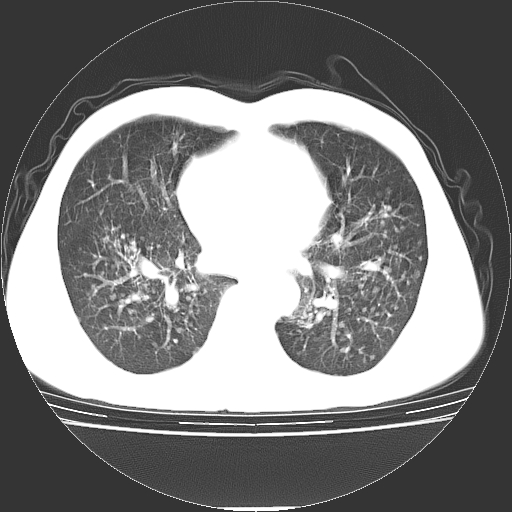

以下是引用yangyudong333在2008-4-29 5:38:00的发言:[br]比较典型的矽肺结节.支持[br]诊断依据:[br] 1.x线表现:[br] ①典型矽肺为多发直径 1~3mm 小结节,即矽结节,由胶原纤维和硅尘构成,可融合成团块,好发于上肺。[br] ②团块周围常有肺大泡。[br] ③胸内淋巴结增大、钙化。如肺门淋巴结呈蛋壳样钙化有助于与其他尘肺区别。[br] ④胸膜常广泛粘连、增厚。[br] 2.ct表现[br] ①两肺散在大小较为一致的小结节影,其密度较高,边界清楚。[br] ②小结节可融合为较大团块影,直径约 1cm ,甚至可达 10cm以上,易发生在上叶。[br] ③小结节周围常并有小叶中心气肿或弥漫性肺气肿。

以下是引用liuyue在2008-4-28 22:30:00的发言:[br]比较典型的矽肺结节.[br]请结合临床及化验除外矽肺合并肺结核之可能.